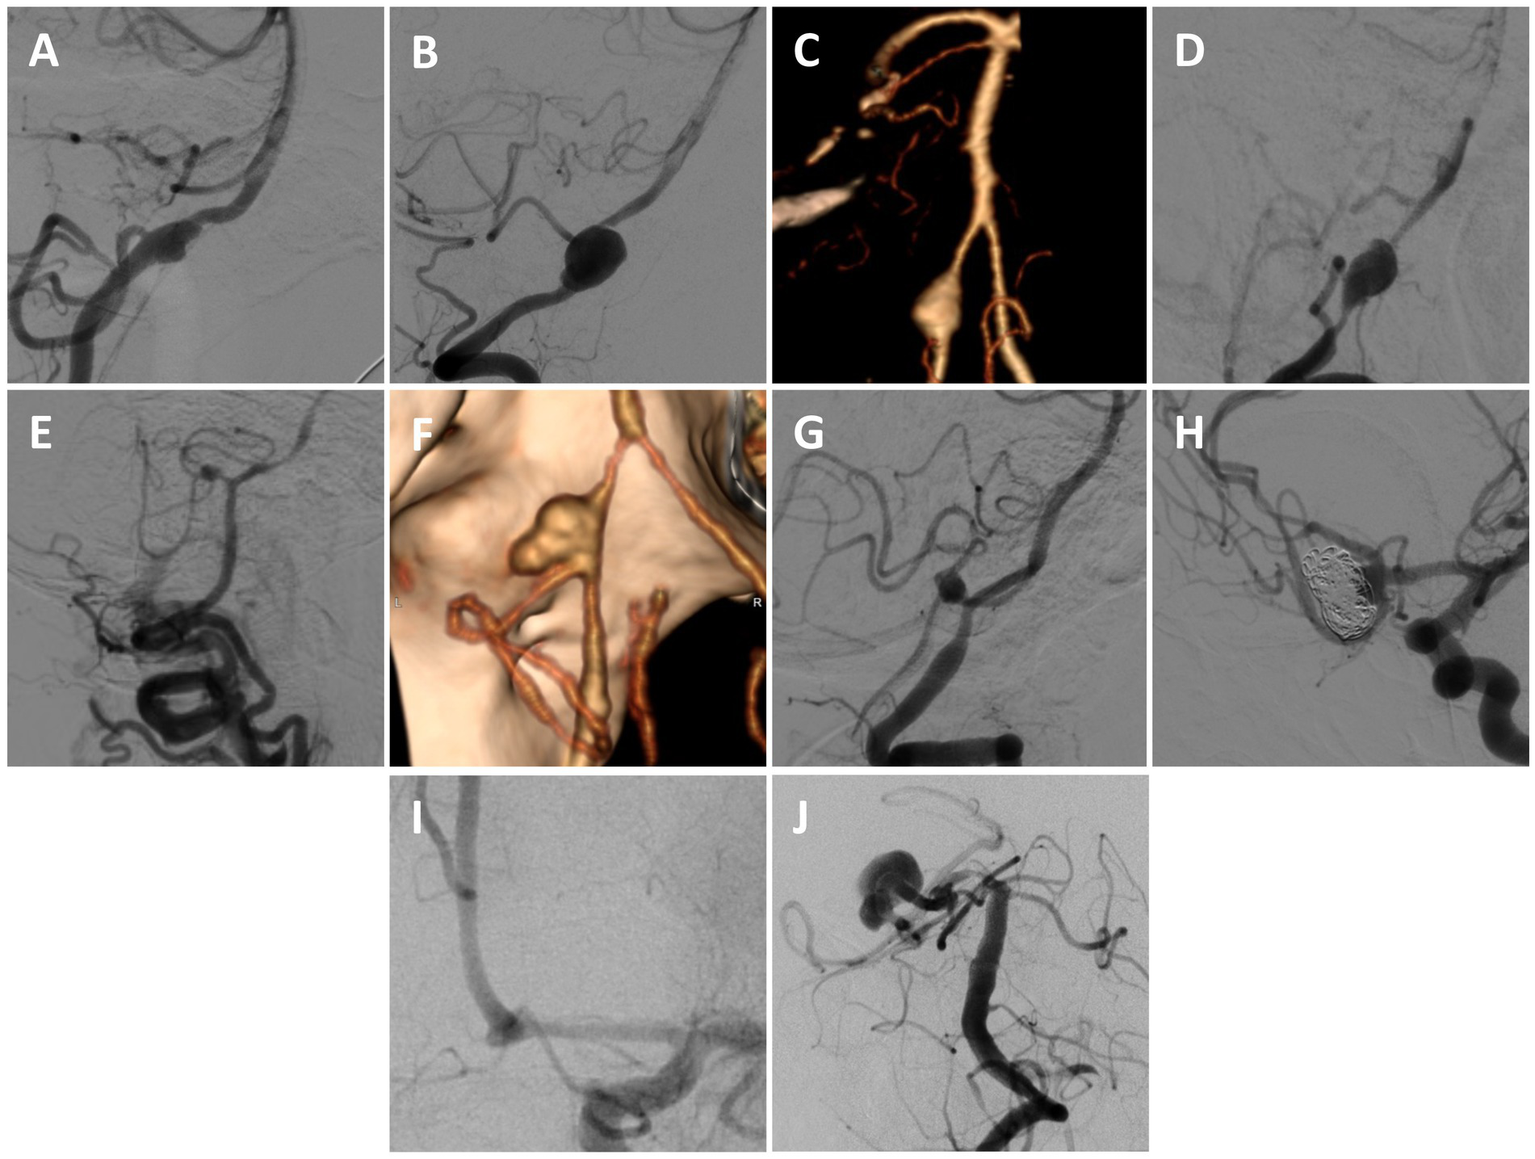

Figure 1

Treated aneurysms. (A) Left VA fusiform ruptured aneurysm involving the proximal left PICA (lateral angiogram of left VA). (B) Right VA fusiform ruptured aneurysm involving the proximal right PICA (lateral angiogram of the right VA). (C) Left VA fusiform ruptured aneurysm involving the proximal left PICA (3D-reconstruction). (D) Right VA fusiform ruptured aneurysm involving the proximal right PICA (lateral angiogram of the right VA). (E) Right proximal AICA/PICA fusiform ruptured aneurysm involving the vessel origin (lateral angiogram of the right VA, also demonstrating an iatrogenic right cervical VA-venous fistula from an unsuccessful prior endovascular treatment attempt). (F) Left VA fusiform ruptured aneurysm involving the proximal left PICA (3D-reconstruction). (G) Left proximal PICA fusiform ruptured aneurysm (lateral angiogram of left VA). (H) Recurrent ruptured and partially coiled Acomm aneurysm arising from an azygous left A1 (oblique angiogram of the left ICA). (I) Left A1-2 junction traumatic ruptured pseudoaneurysm (oblique angiogram of the left ICA). (J) Large right fusiform P2 aneurysm with a proximal dysplastic P1 (AP angiogram of the left VA).